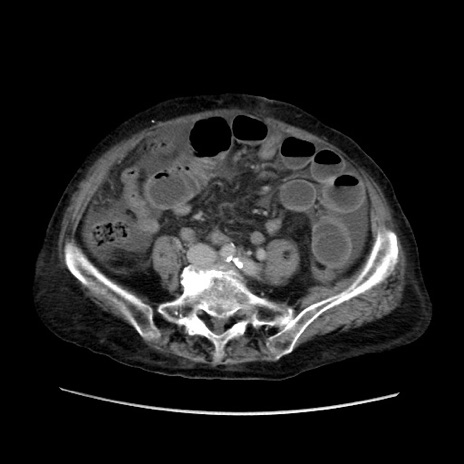

症例31(横断像)

【症例】80歳代 女性

【主訴】腹部膨満感

【現病歴】他院にて肝硬変にてフォロー中。1週間前から便秘、腹部膨満感、臍部腫瘤あり受診となる。

【既往歴】肝硬変

【身体所見】腹部膨隆あり、皮膚変化なし、疼痛なし。

【データ】WBC 4600、CRP 0.25